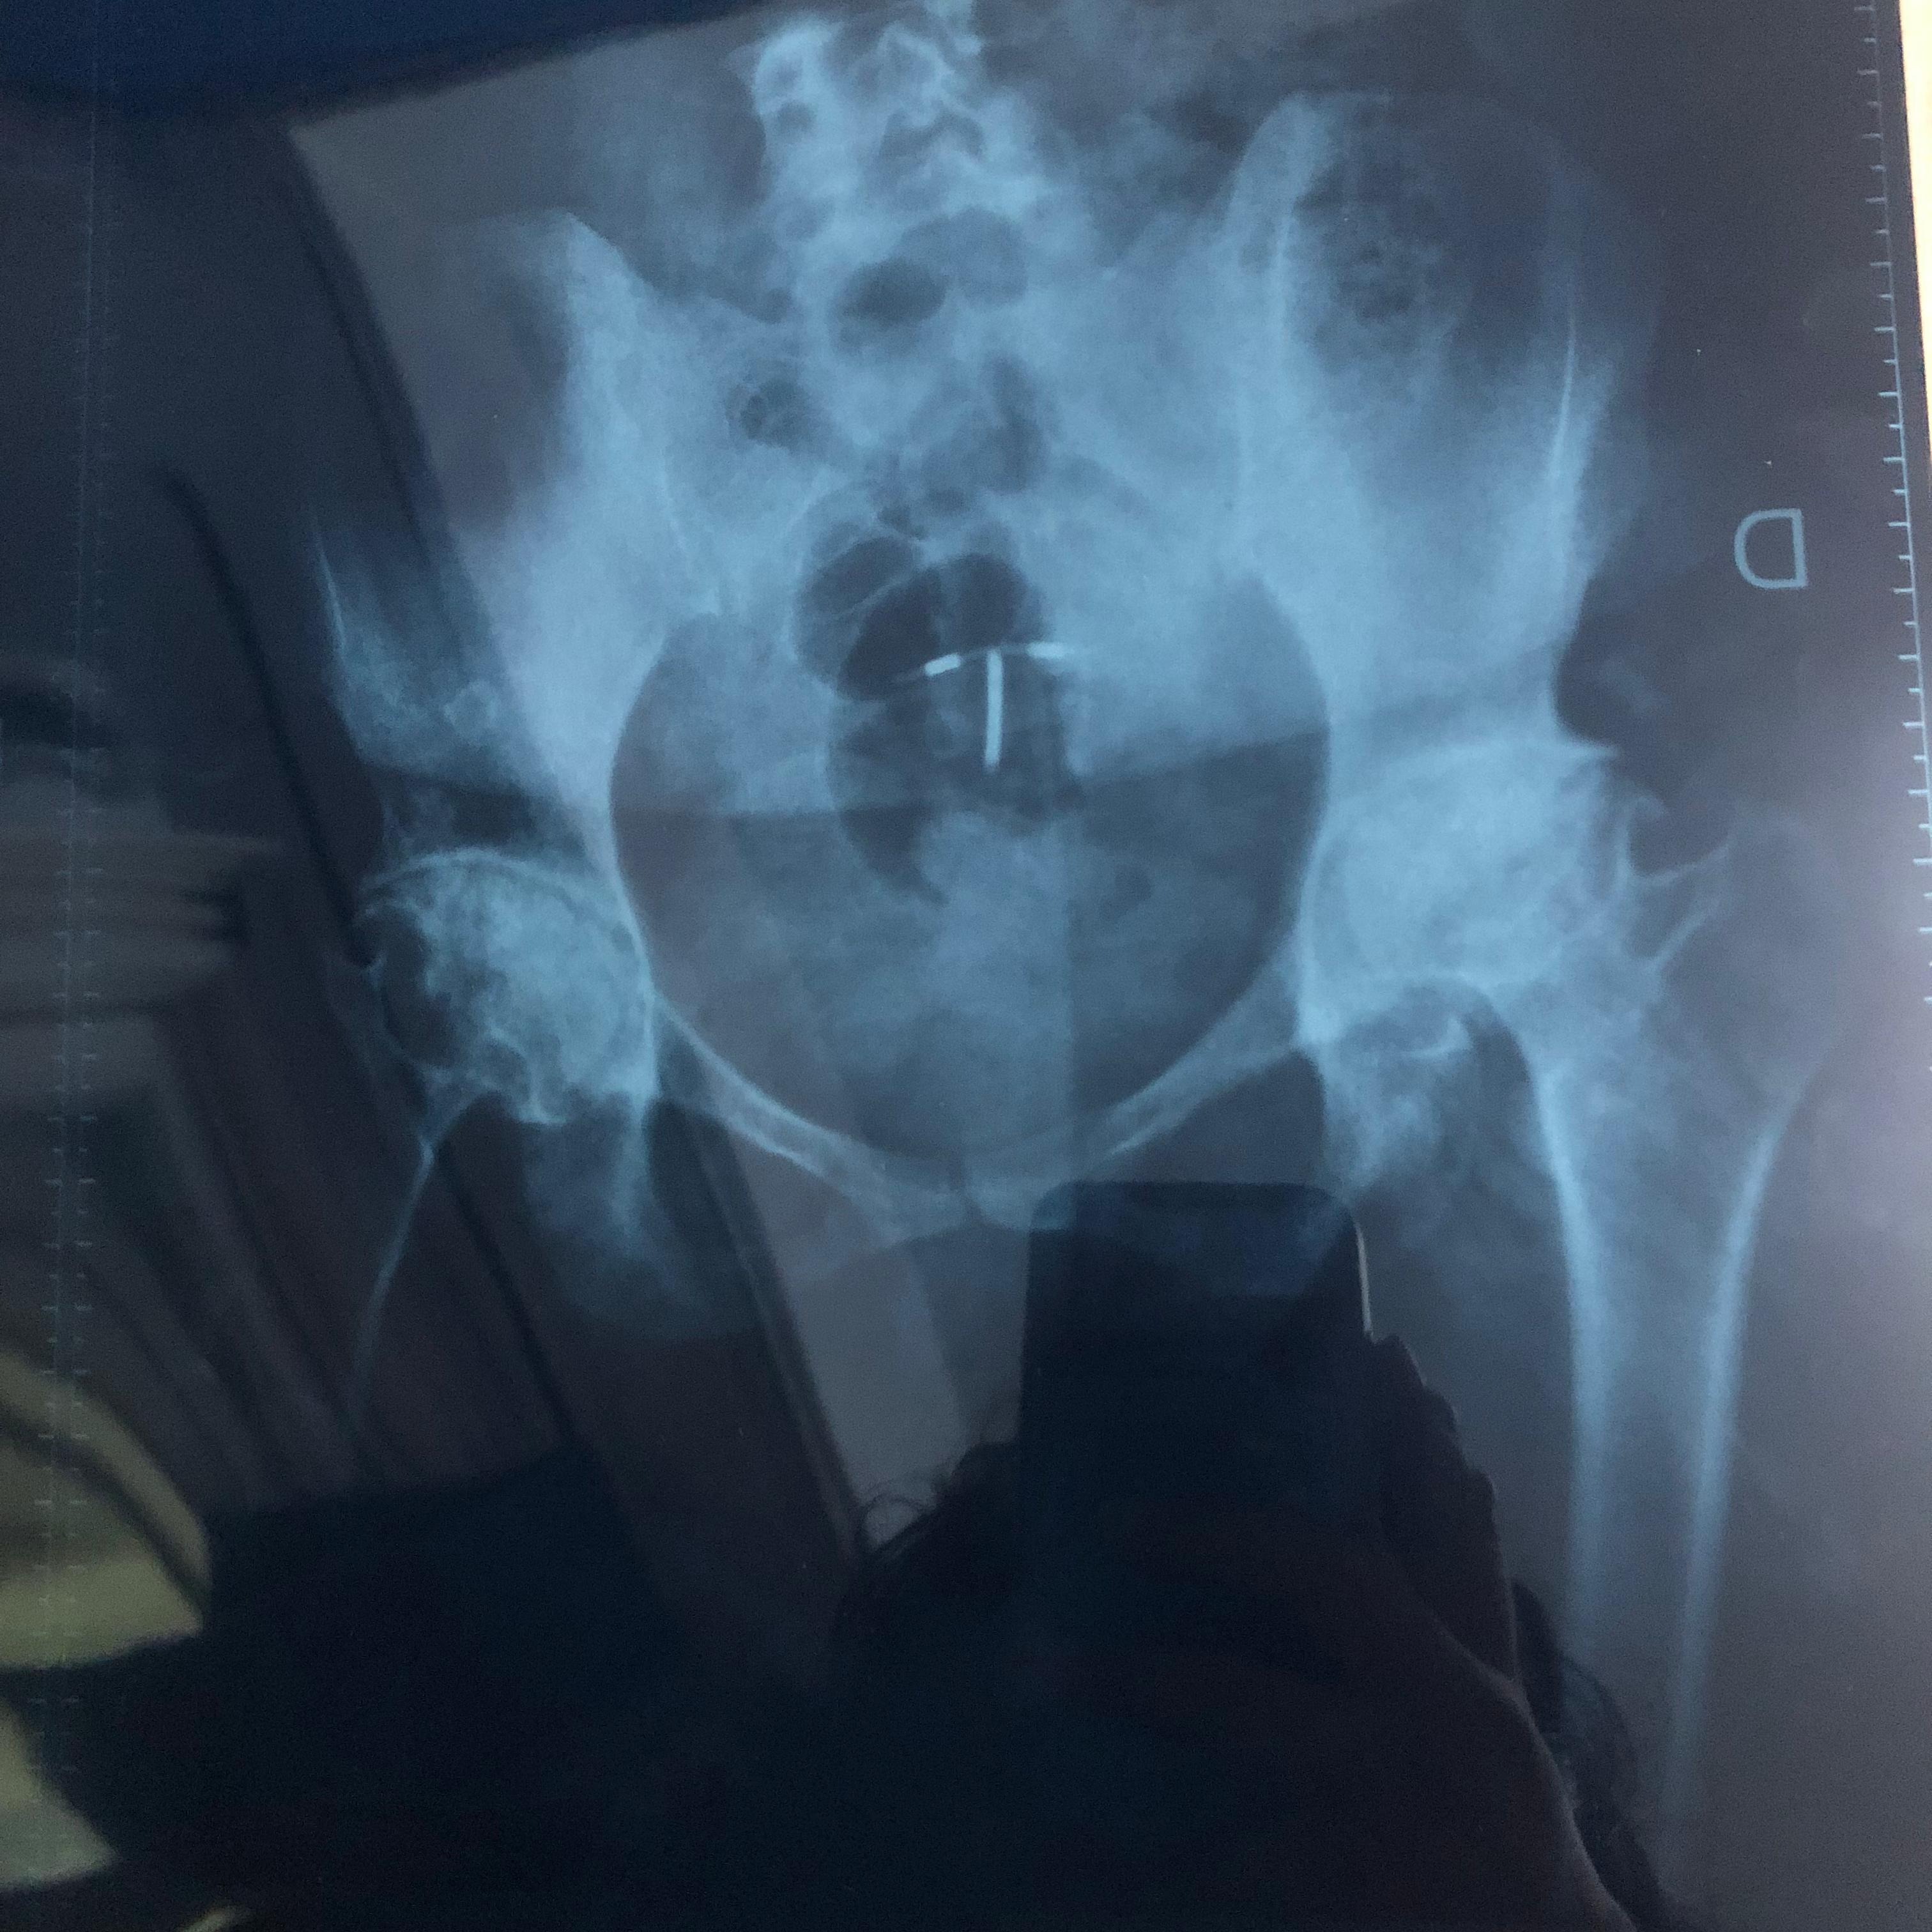

Soy Venezolana y nací con artritis Reumatoidea Juvenil, actualmente tengo 33 años, mi enfermedad a evolucionado a artritis Reumatoidea gotosa y en muchas partes ya tengo artrosis.

Hoy necesito prótesis en ambas caderas y ambas rodillas, las cuales son de reemplazo total.

Me fui de Venezuela a Argentina porque me dijeron que acá podrían ayudarme y aunque pueden operarme, no me pueden dar las prótesis adecuadas para mí condición de salud y edad. Las que me recomiendan son las de mejor calidad, durabilidad y por ende las más costosas!!. (Bioimpianti italiana ip magnam o Artrotek maxx americana. Para reemplazo total de rodillas y caderas)